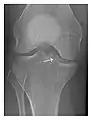

High-energy trauma fractures

Occult osseous injuries may result from a direct blow to the bone by compressive forces of adjacent bones against one another or by traction forces during an avulsion injury. Lesions in the tibial plateau, hip, ankle, and wrist are often missed. In a tibial plateau fracture, any disruption of the posterior and anterior cortical rims of the plateau should be sought. Impaction of subchondral bone will appear as an increased sclerosis of the subchondral bone (Figure 1). In the hip, posterior acetabular fractures also present subtle radiographic findings. The acetabular lines should then be carefully examined keeping in mind that the posterior rim, which is harder to see on X-rays, is more frequently fractured than the anterior rim (Figure 2). In the wrist, detection of carpal bone fractures is often challenging, with up to 18% of scaphoid fractures radiographically occult. Carpal fractures, especially the scaphoid, are associated with the risk of avascular necrosis. In apparently normal wrist radiographs from symptomatic patients, if there is history of a fall on an outstretched hand with pain in the anatomic snuffbox, suggesting scaphoid injury, the initial examination with posteroanterior, lateral, and pronation oblique views must be complemented by other specific views such as supination oblique and the "scaphoid" view A careful examination of cortices for evidence of discontinuity or offset and cancellous bone for lucency is necessary (Figure 3).[1]

a

b

c

Figure 1: A 56-year-old woman presenting with left knee pain after a fall. (a) Initial anteroposterior radiograph was considered normal, however, subtle cortical disruption of the anterior rim of the medial tibial plateau, medial to the tibial spine, is noted (arrow). (b) Coronal T1-weighted MRI confirms the cortical disruption (arrow) and shows extensive fracture through the proximal tibia. (c) Coronal proton density-weighted image with fat saturation shows extensive edema in the subchondral bone. Note also hypersignal adjacent to the medial collateral ligament corresponding to a grade I sprain (arrowheads).[1]